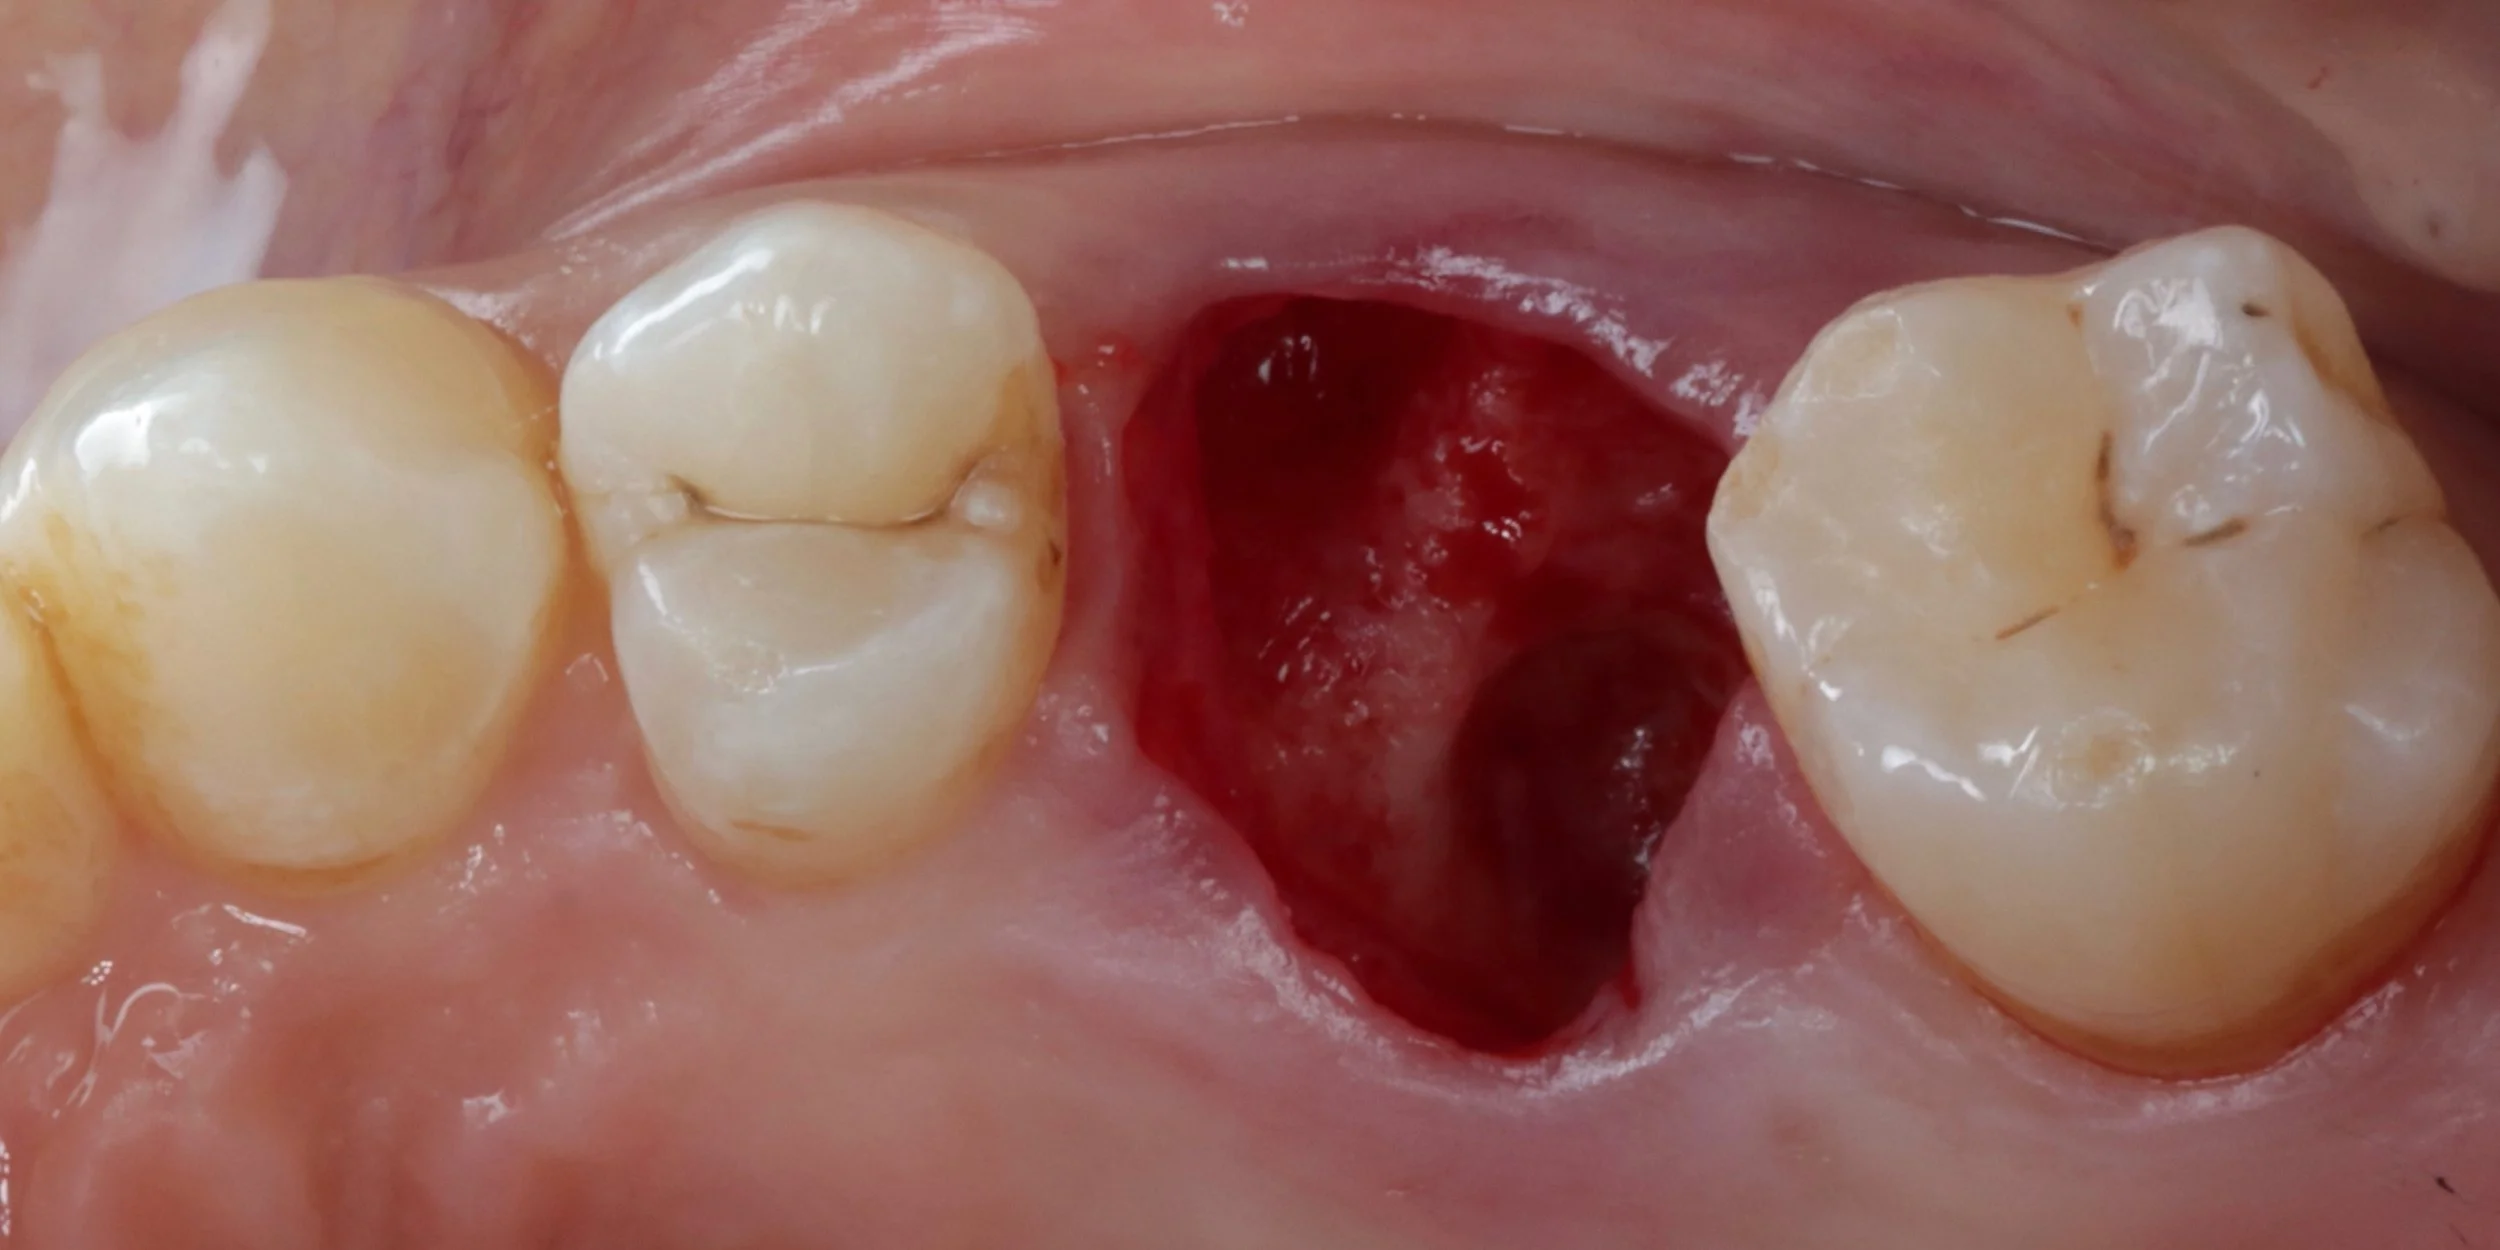

This under utilised yet highly valuable skill forms the foundations to help maintain gingival and alveolar architecture. From the general to the implant dentist, 15c will provide you with a predictable and simplified approach to ensure you can cultivate the ideal conditions for future implant or bridge placement for your patients. Learn surgical tips to improve your extraction and suturing techniques. Become confident in socket debridement and cleansing. Understand and see the different biomaterials available & the advantages and disadvantages of each. Practice how to use all of these skills to neatly and confidently perform ridge preservation in practice.